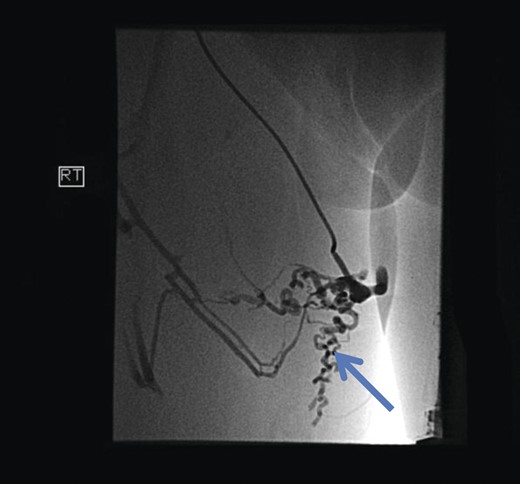

The superficial external pudendal vein was embolized with 1% sodium tetradecyl sulphate and then coiled through a contralateral puncture under fluoroscopic guidance (Figs 3 and 4). The procedure went uneventfully with successful obliteration of the communicating thigh veins to vulval varices (Fig. 5) and the patient was discharged home the same day.

Post-procedure fluoroscopy showing successful obliteration of communication of thigh veins to vulval varices (blue arrow).